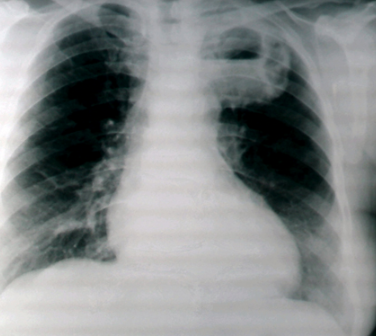

An 88yo lady with an altered conscious state and who is immunosuppressed develops a high grade fever with a cough productive of foul-smelling sputum. On examination, cavernous breath sounds are heard over an area of the lung

Acute lung abscess

Other causes: pulmonary infarcts, malignancies, penetrating trauma, necrotising pneumonias, bronchial obstruciton